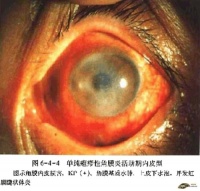

3、临床表现[编辑 | 编辑源代码]

主观症状有疼痛、羞明,流泪和视力模糊,严重时甚至仅有光感。本病多为慢性病程,在病变的最早期可在裂隙灯下发现角膜内皮水肿和少量细小沉着物。实质内有轻微细胞浸润。随着症状的出现,患者可有眼睑痉挛及睫状充血。

角膜病变可由周边部开始,也可由角膜中央部开始。但以前者较为多见。

由周边起始者,角膜边缘首先发暗,出现轻微混浊,多由角膜上方开始,逐渐向中心扩展。这种混浊居于深层,呈灰白色。上皮水肿,可有水疱形成。临近的睫状血管迅即充血,并开始由角膜边缘向内发展。角膜边缘因水肿呈隆起状,形如军官的肩章称为肩章血管翳。当角膜周边水肿消退后,睫状血管迅即消失。但角膜缘的深层血管向角膜中央伸入,有似推动混浊向前进展之势。这些血管居于角膜深层,呈典型的毛刷或扫帚状,直而平行,不相吻合。可持续十数年之久,终则硬化。同时角膜边缘他处亦发生类似混浊,并向中心进展。这种弥漫混浊迅速广泛发展,以致全角膜发暗,失去光泽。如果用裂隙灯检查,则见角膜水肿变厚;角膜深层灰色混浊呈雪片状,细小点状或线条状。经2~4周后达到最高峰。此时角膜表面呈云雾状,极似毛玻璃。严重患者,角膜极为混浊,甚至虹膜完全被遮盖而不能见。这个进展期亦可延长数月而达高峰。

由中央起始者,首先侵犯角膜中部,角膜深层出现灰色雪片状、细小点状或线条状混浊。角膜表面光滑、晦暗,无光反射,混浊逐渐增加,由中央持续向周边进展,终则达到边缘,以致角膜完全变为混浊。虽然如此,但中央部混浊仍较周边部者更为致密。当混浊进行至边缘时,血管即开始由各方向进入角膜缘。这些都是深层血管,呈毛刷状或扫帚状。当炎症达最高峰时,角膜完全混浊。因角膜深层布满血管,又被角膜灰色混浊所被覆,故呈一致性污红色,如红布状。此时难以看见虹膜组织,同时视力减退至眼前指数或手动。炎症高峰期经历约2~4个月即进入退行期。混浊首先由角膜边缘消退,角膜逐渐恢复透明,血管变细甚至闭塞。唯中部混浊持续最久,终则消退,仅留极少淡薄混浊和一些深层血管,对视力影响不大。多年后仍能根据角膜的深层混浊及遗留的毛刷状血管诊断患者曾罹此病。退行期需半年甚至一年或更长时间方能终止。